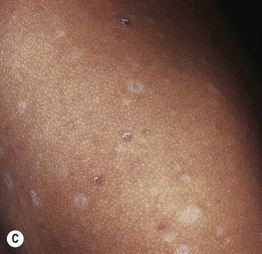

• Postinflammatory hypopigmentation is a very common skin disorder that follows a wide variety of dermatoses, most commonly atopic dermatitis, seborrheic dermatitis, and psoriasis, as well as pityriasis lichenoides chronica, lichen striatus, and lichen sclerosus (Fig. 54.15).

Fig. 54.15 Postinflammatory hypomelanosis. Hypopigmentation secondary to psoriasis (A), seborrheic dermatitis in an infant (B), pityriasis lichenoides chronica (C), lichen striatus (note the flat-topped papules) (D), and hypopigmented mycosis fungoides (E). Complete pigment loss in patients with severe atopic dermatitis (F), discoid lupus erythematosus (G), and neonatal lupus erythematosus (H). B, Courtesy, Jean L. Bolognia, MD. H, Courtesy, Julie V. Schaffer, MD.

• It typically coexists or co-localizes with the inflammatory lesions, but occasionally only hypopigmented lesions are seen; the size, shape, and distribution pattern often provide clues to the underlying inflammatory dermatosis.

• Most commonly there is a decrease in pigmentation; rarely there is an absence (e.g. severe atopic dermatitis).